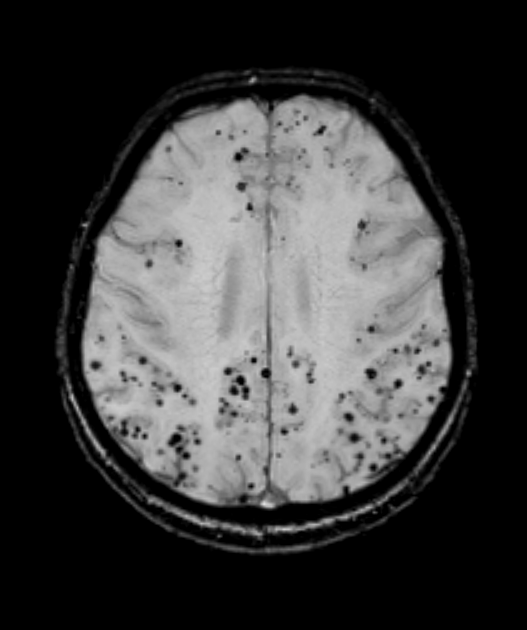

- A 75-year-old patient presented with left sided weakness.

- MRI showed an acute infarct in the right corona radiata.

- SWI showed florid microhaemorrhages in a mixed distribution - both deep (likely representing hypertensive arteriolosclerosis) and lobar (likely representing cerebral amyloid angiopathy).